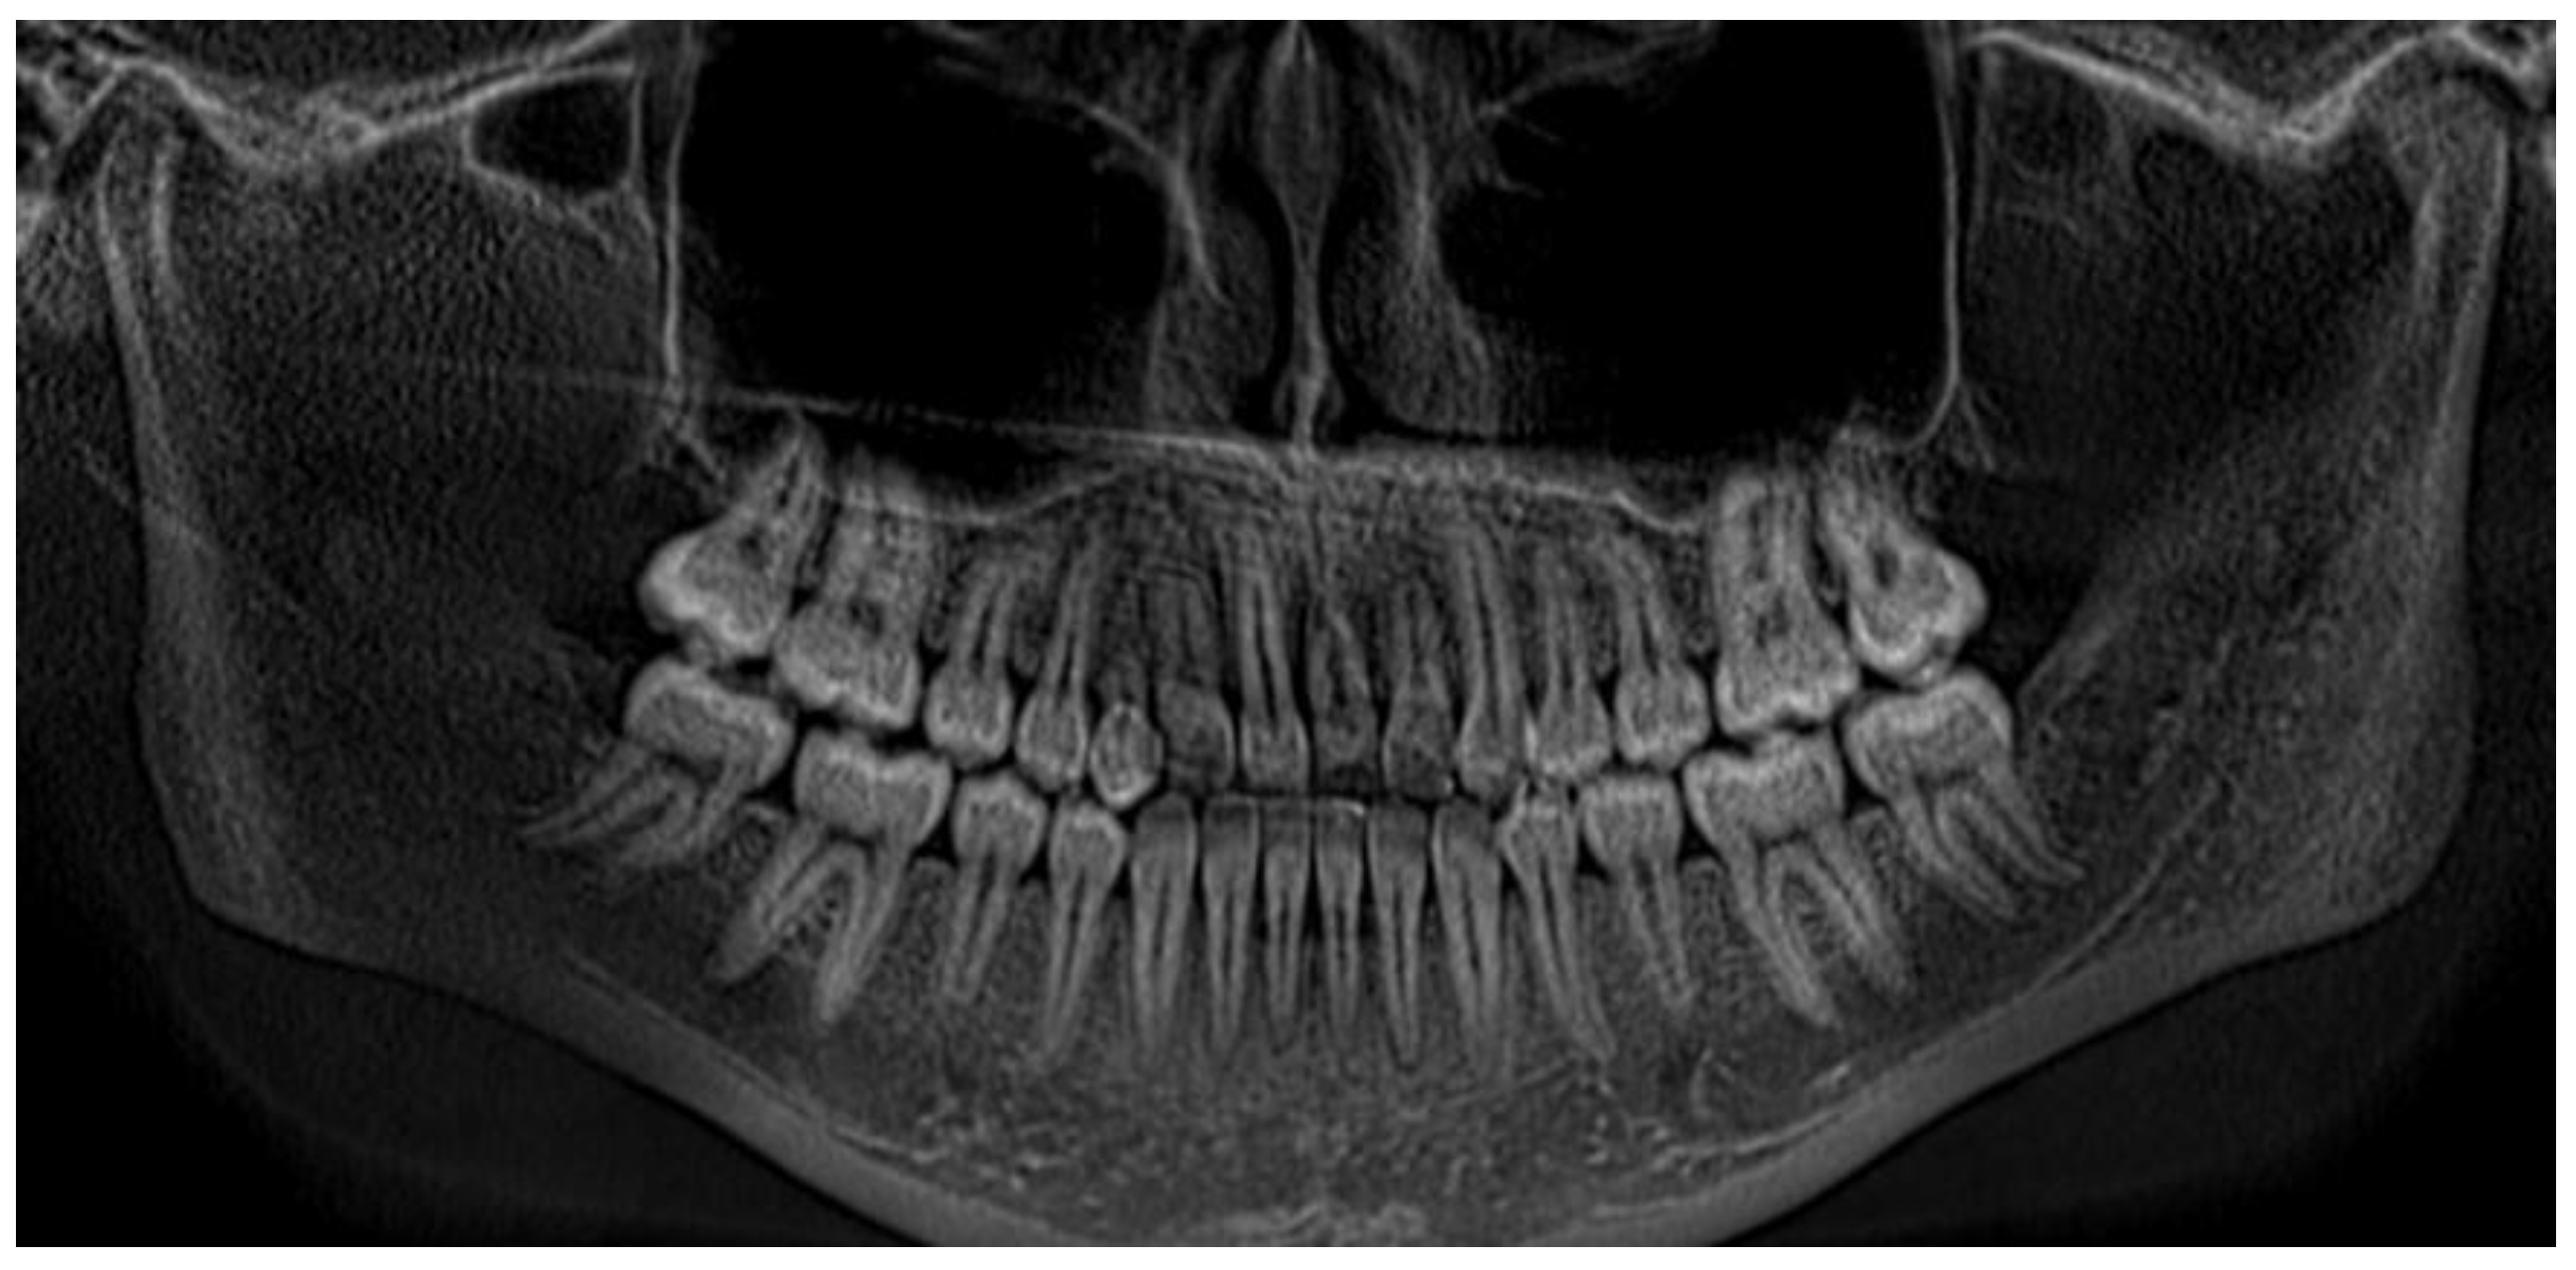

| Pinho T., Amaral R. 2025 | ♀ 13 YO | Mx.C.I1 | C | R | V (impacted) | Cl I | Maintained | -Total root resorption of tooth #11 due to the position of the ectopic canine |

3.2. Clinical Case